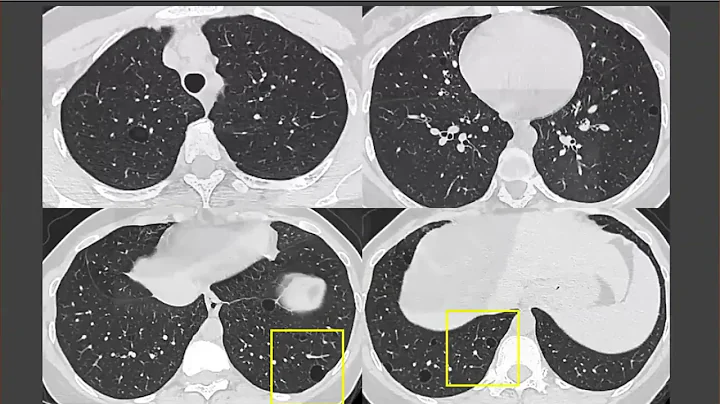

Pulmonary Langerhans Cell Histiocytosis (plch) On Ct

Nice example of how earlier on in disease, it is easier to make a confident diagnosis in ILD cases. Also, classic appearnce of ...